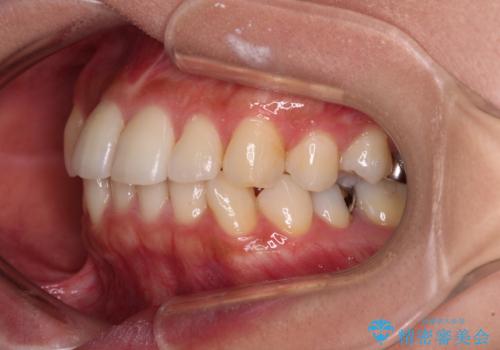

- 前歯のクロスバイトと口元の膨らんだ横顔の印象を気にして来院された患者様です。

ご本人の気にされている口元は、分析数値からするとそれほど突出しているものではありませんでした。

しかしながら。そのまま叢生を解消すると横顔が突出した印象になる可能性が高かったため、上下左右の小臼歯4本を抜歯して、ワイヤー装置にて矯正治療を行うこととしました。